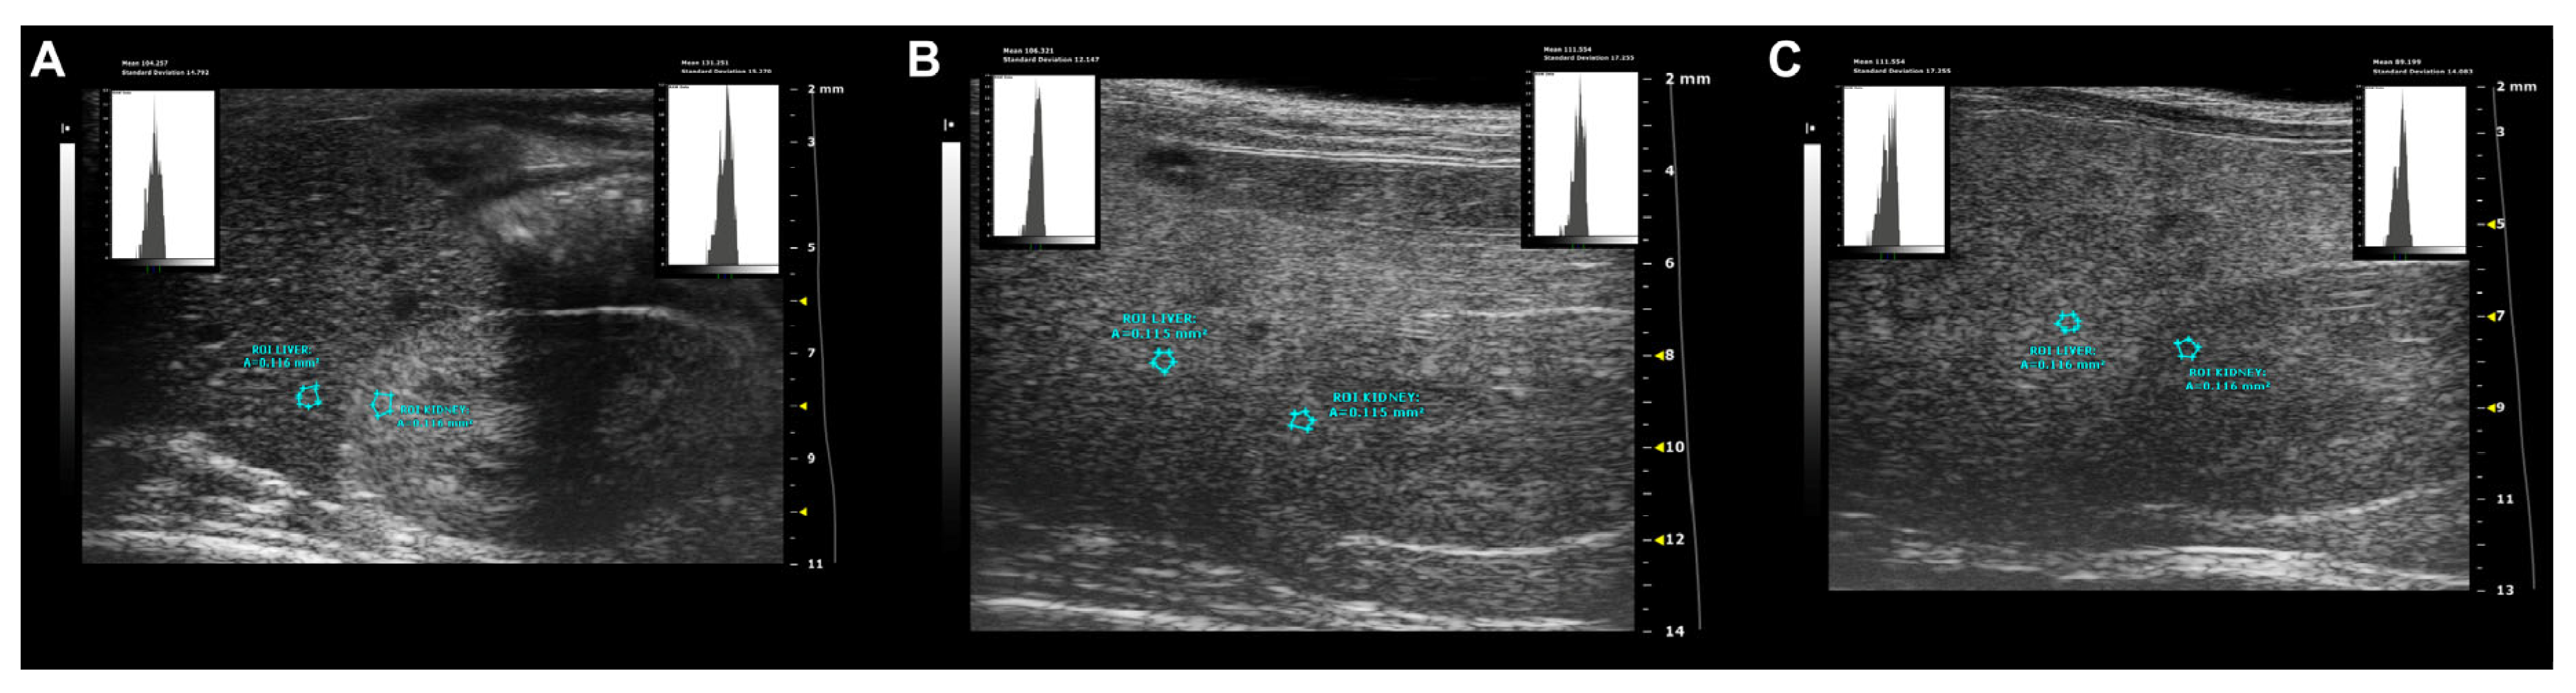

- Parametric analysis: Overall, normal hepatic parenchyma is less echogenic than the right renal cortex in rodents [7]. The hepatic echogenicity increases due to the presence of fatty infiltration and/or fibrosis, changing the relation between the liver and the right renal cortex [12].

- Hepatic-renal ratio (HR): A longitudinal view was acquired in order to have both the liver (caudate lobe) and the right kidney clearly visualized. Liver echogenicity was compared with that of the renal parenchyma, to normalize differences in the overall ultrasound gain value used for the acquisitions. A region of interest (ROI, (0.1 ± 0.02 mm2) was manually drawn and placed in the liver parenchyma, avoiding focal hypo- and hyperechogenicity. A second ROI was positioned in correspondence with a portion of the renal cortex devoid of large vessels along the focusing area of the image at the same distance from the probe to avoid distorting effects in ultrasonic wave patterns. HR values were obtained by dividing the mean grey level of the hepatic ROI for that obtained for the renal one (pixel intensity = average intensity/mm2, arbitrary units, a.u.) [9,44].